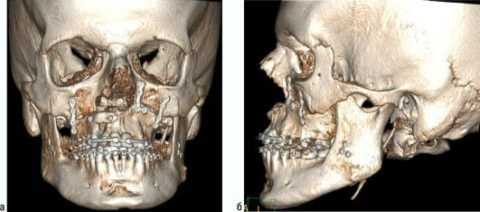

В последнее время стоматологи-онкологи начали активно применять компьютерную томографию, которая позволяет обнаружить участки атипичного окостенения за пределами челюсти. С помощью этой методики специалист также оценивает размер, форму и точное расположение злокачественного новообразования.

При экзофитном типе роста опухоль представлена разрастаниями с признаками изъязвлений. Кратерообразная язвенная поверхность встречается при эндофитном росте злокачественного новообразования. На поздних стадиях рака верхней челюсти выявляют деформацию альвеолярного отростка, патологическую подвижность интактных зубов, отсутствие болевой и тактильной чувствительности в зоне локализации опухоли. Прорастание злокачественного новообразования в орбиту ведет к развитию экзофтальма, становится причиной потери зрения.

На R-граммах нижней челюсти - деструкция более одной анатомической части нижней челюсти с наличием патологического перелома.